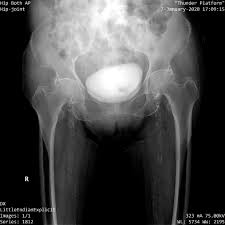

• 사타구니가 깊게 아픔 : “관절 안쪽” 느낌이 강하면 고관절 자체 문제(관절염, 충돌증후군, labrum 등) 가능성을 생각합니다.

• ‘딸깍’ 소리, 걸림/잠김 느낌 : 깊은 사타구니 통증과 함께 나타나면 관절 내 문제를 의심하기도 합니다.

Q3. 사타구니가 깊게 아프면 더 위험한 건가요?

A. “위험”이라기보다 고관절 관절 내부 문제를 시사할 수 있어요. 움직임 제한, 걸림/딸깍이 함께 있으면 진료로 확인하는 게 좋습니다.